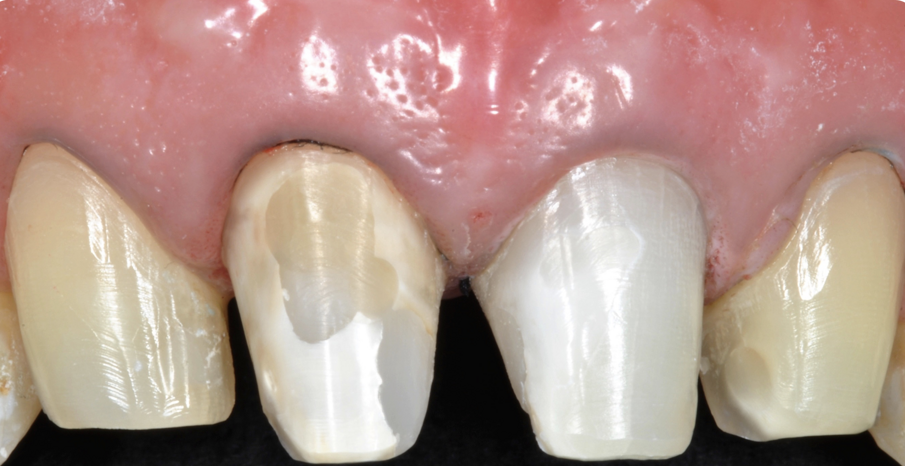

Fig. 12 - Trascorsi 7 mesi dalla chirurgia e dalla risoluzione del problema endodontico, si è proceduto con la preparazione a butt-joint del 12 e del 22 per ricevere due faccette e delle preparazioni complete a finire su 11 e 21 per le due corone monolitiche in disilicato.

Fig. 13 - Il manufatto protesico ultimato pre cementazione.